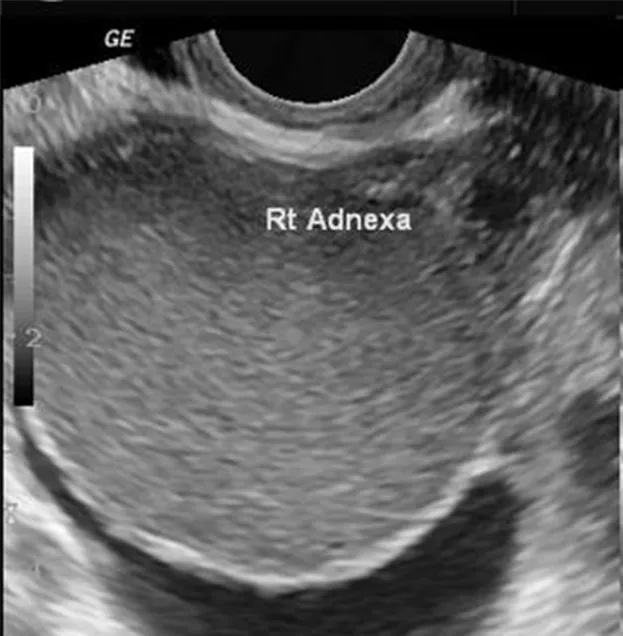

28세 산과력 2-0-1-2인 여성이 불임으로 병원을 찾았다. 그녀는 보통 28일 주기로 생리를 하며, 마지막 출산 이후부터 생리통이 더욱 심해졌다고 호소했다. 골반 초음파 검사 결과 자궁은 정상 크기를 보였고, 왼쪽 난소의 초음파 이미지는 아래와 같다. 아래는 여성의 혈액검사 결과이다. 적절한 치료 방법은 무엇인가?

• 불임을 주소로 내원한 환자이다. 시행한 골반초음파에서 균질한 저에코의 단방성 낭종이 관찰된다.

• 월경통 악화, CA-125 상승을 볼 때 자궁내막종을 의심할 수 있다.

• 확진 및 불임 치료를 위해 난소낭종절제술을 시행한다.